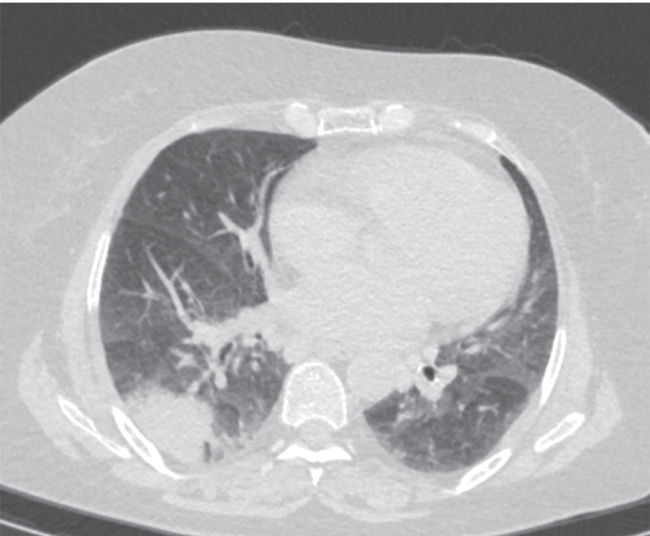

「在我们本地医院看了下一直没好,这两天有点喘不上气。听说咱这医院大,就再来看看。」患者拿出了在外院拍的片子,CT显示双侧肺部炎症,可见支气管充气相,少量胸腔积液。主任做了个听诊,简单开了些检查,便让他下午来办住院。

胸部CT 影像资料(图片仅作示例,非本病例资料)

图源:参考资料5